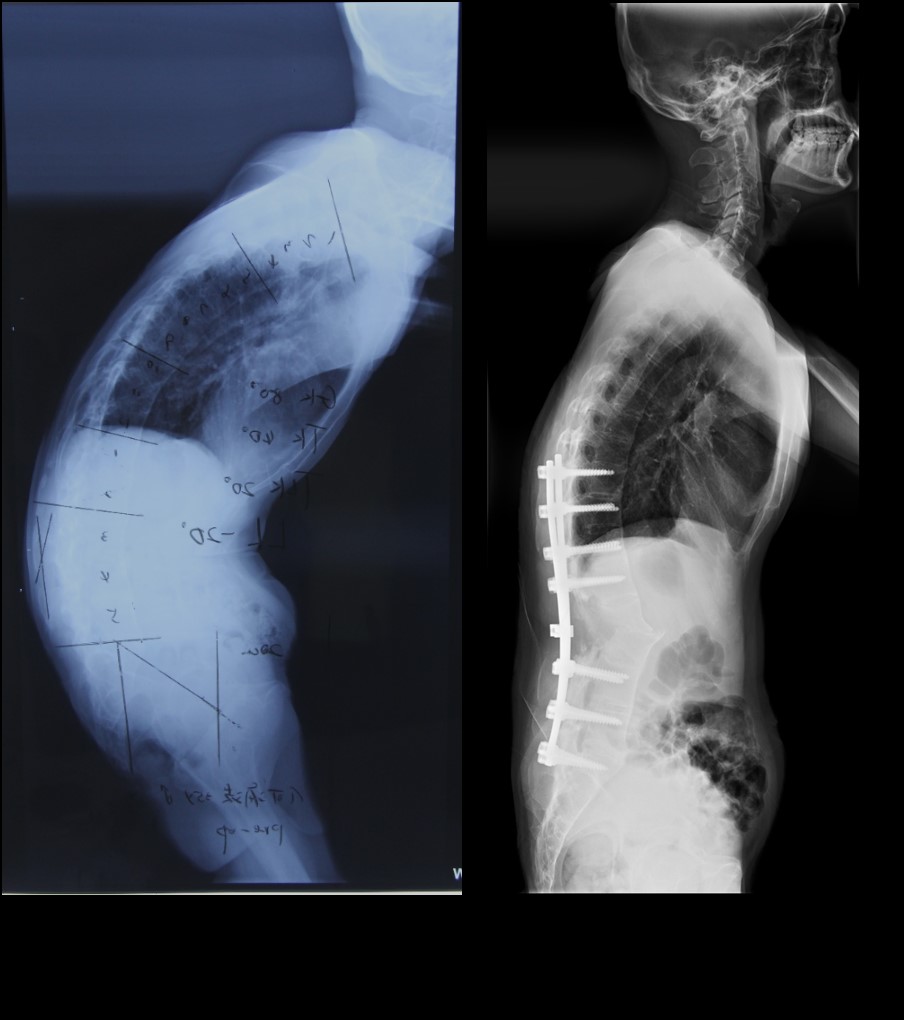

湘雅三医院骨科脊柱组专家李志跃副教授、张朝跃教授接待了何先生及其家属,详细了解病情后,组织科室骨干力量研究手术方案。本例患者畸形非常独特,不但有60°左右的后凸畸形,同时合并严重的侧凸与旋转畸形,手术难度更大。患者年龄轻,期望值较高,对手术效果提出了较高要求。湘雅三院骨科脊柱组的专家们已经多次利用3D打印技术帮助解决临床问题,积累了相当宝贵的经验。本次再度与华翔增量的工程师通力合作,对两种手术方案进行模拟演示,比较矫形效果。手术方案一:截骨节段选择腰3,优点是避开了脊髓圆锥,相对安全,缺点是矫形力度不够,无法矫正侧凸和旋转畸形。手术方案二:截骨节选择后凸和侧凸旋转最明显的腰1、2,做非对称的“V”形截骨,虽然一个半节段的差异,矫形优势却相当明显,既能矫正后凸畸形又能改变侧凸旋转畸形,缺点是截骨椎体量大,容易伤及脊髓圆锥,甚至导致不可逆转的下肢瘫痪,手术组的专家感受到空前的压力。

最终,湘雅三医院脊柱团队克服重重困难,顶住压力,采用了风险更大的矫形方案,选择在腰1、2节段行非对称的“V”形截骨。在华翔增量工程师制作的3D打印截骨导板帮助下,手术医生精确定位截骨椎体,截骨角度和深度和术前模拟完全吻合,整个截骨过程一气呵成。术前扭曲得像棵“歪脖子树”的何先生,术后第三天重新挺直了腰杆,在病房昂首阔步,引得病友们啧啧称奇。

据手术医生李志跃副教授介绍,相比依靠经验的传统截骨手术,利用3D打印截骨导板辅助的截骨手术优势明显,不但手术时间缩短,出血量大大减少,最重要的是截骨精度大大提高,术后矫形效果令医生和患者都非常满意。